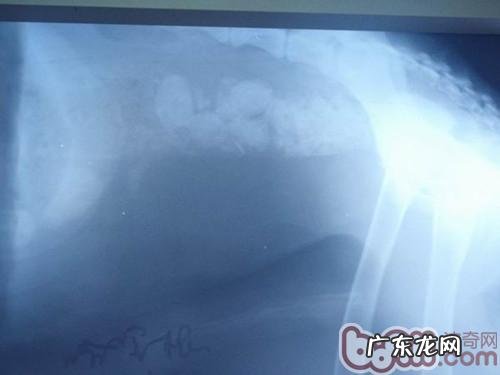

它是一例一岁的德国牧羊犬(详细介绍),乡村喂养,主人家已不家,动物饲养员每日给喂养狗粮,随后在给几片骨骼磨牙齿,那样不断了只是一周的時间,結果就变为那样,比较严重肠梗堵,必须开展手术医治 。

文章插图

德国牧羊犬肠梗堵